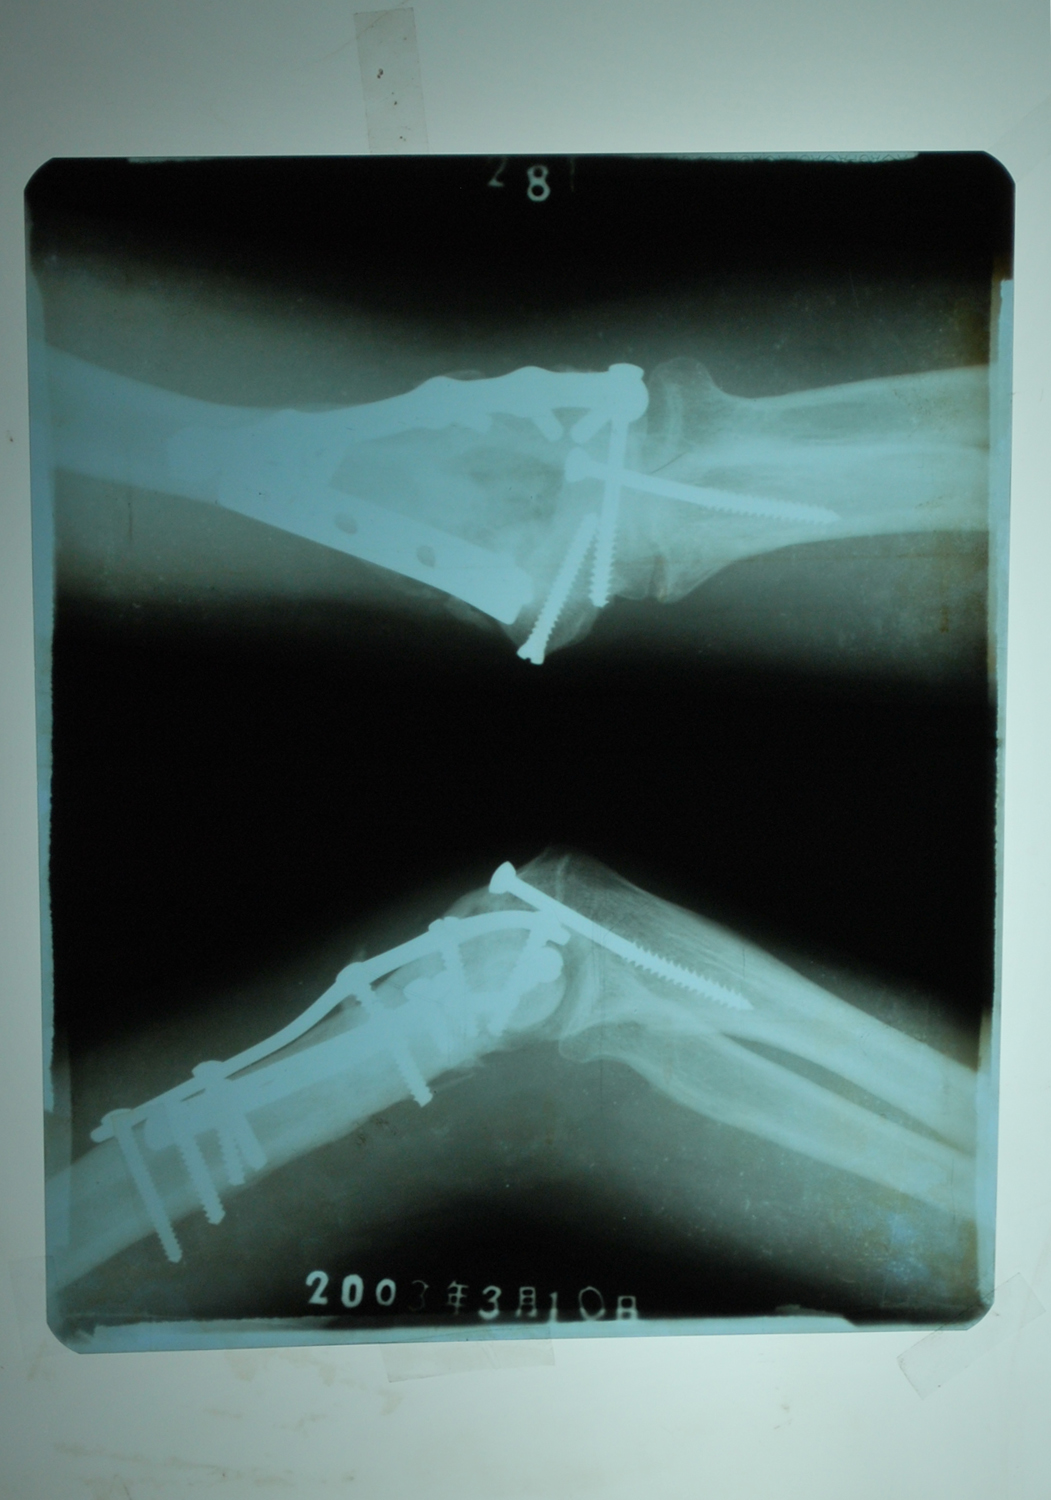

第二天早上,恶警还要给贾志君上绳迫害,贾志君抗议迫害,被迫从公安局三楼跳下。医生诊断右肘骨折,他在伊春医院上两块钢板,十三个钢钉。毫无人性的恶警不顾贾志君死活,上完钢板二天就把他劫持到金山屯区看守所,当时贾志君胳膊肿得很严重,后肘关节僵直不能抬举。贾志君开始绝食抗议迫害,十天后他奄奄一息,人快不行了,狱医秦汉伟敲诈勒索贾志君家属三千元钱,让他办了所谓的保外就医,妻子把贾志君背出看守所。

医生拍的片子显示骨折

至今贾志君的右胳膊还不能回弯不能抬举,洗脸的时候双手不能同时在脸上洗,只能用左手洗脸。